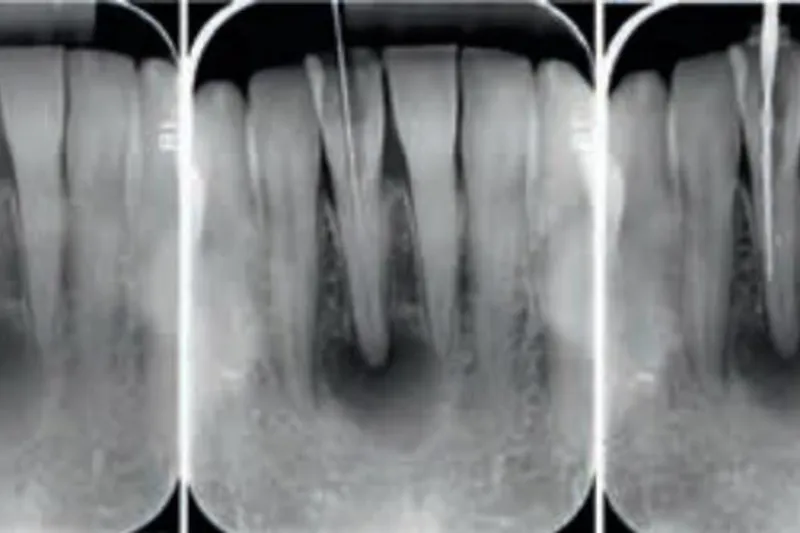

Under endelig udrensning af distale rodkanal i -6 skete fraktur af filstørrelse 40. Den frakturerede filspids efterlades, da den er umulig at fjerne. Ved efterfølgende rodspidsbetændelse pga. den efterladte fil kan det ende ud med ekstraktion af tand.